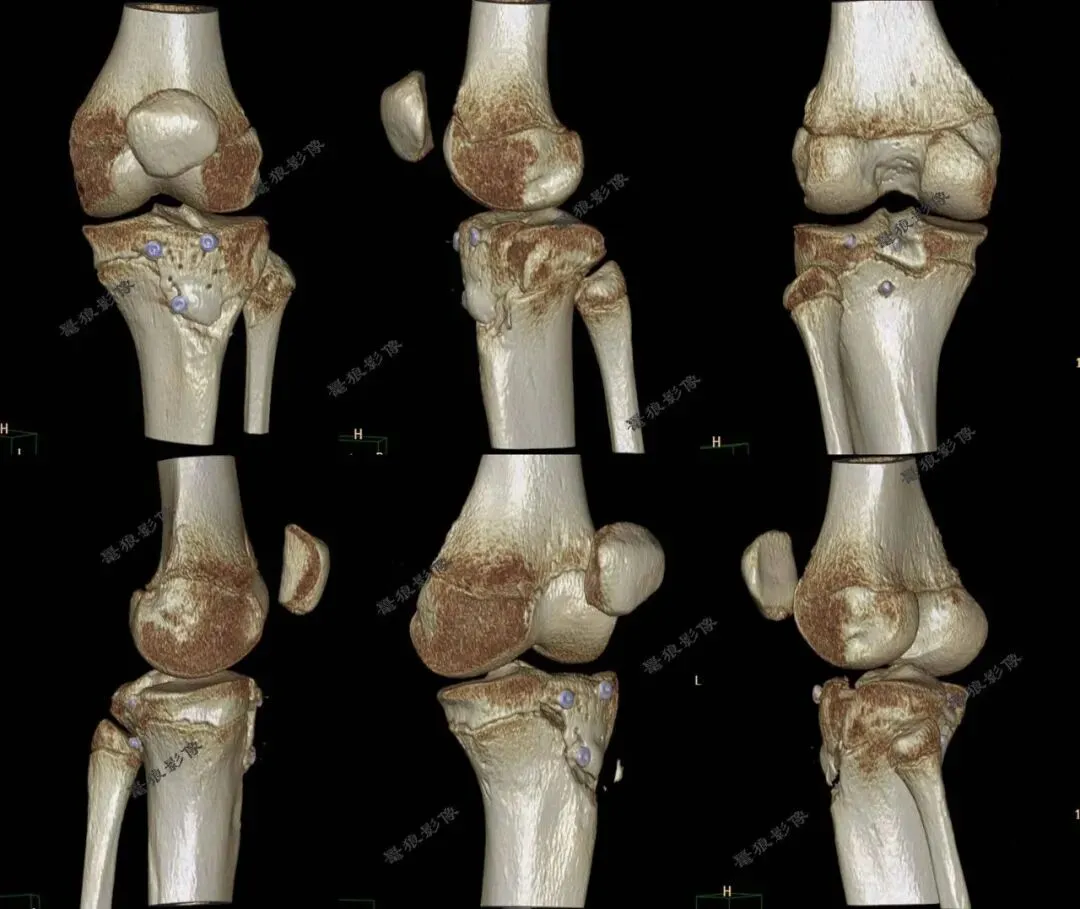

D、胫骨结节骨折病例分享

M,11y。

缘患者入院3小时余前运动后出现左膝部疼痛,活动受限,当时无昏迷,遂送至急诊就诊,查X片:左胫骨结节骺离骨折。

二.术前CT

胫骨结节骨折(OgdenIIIA型 )